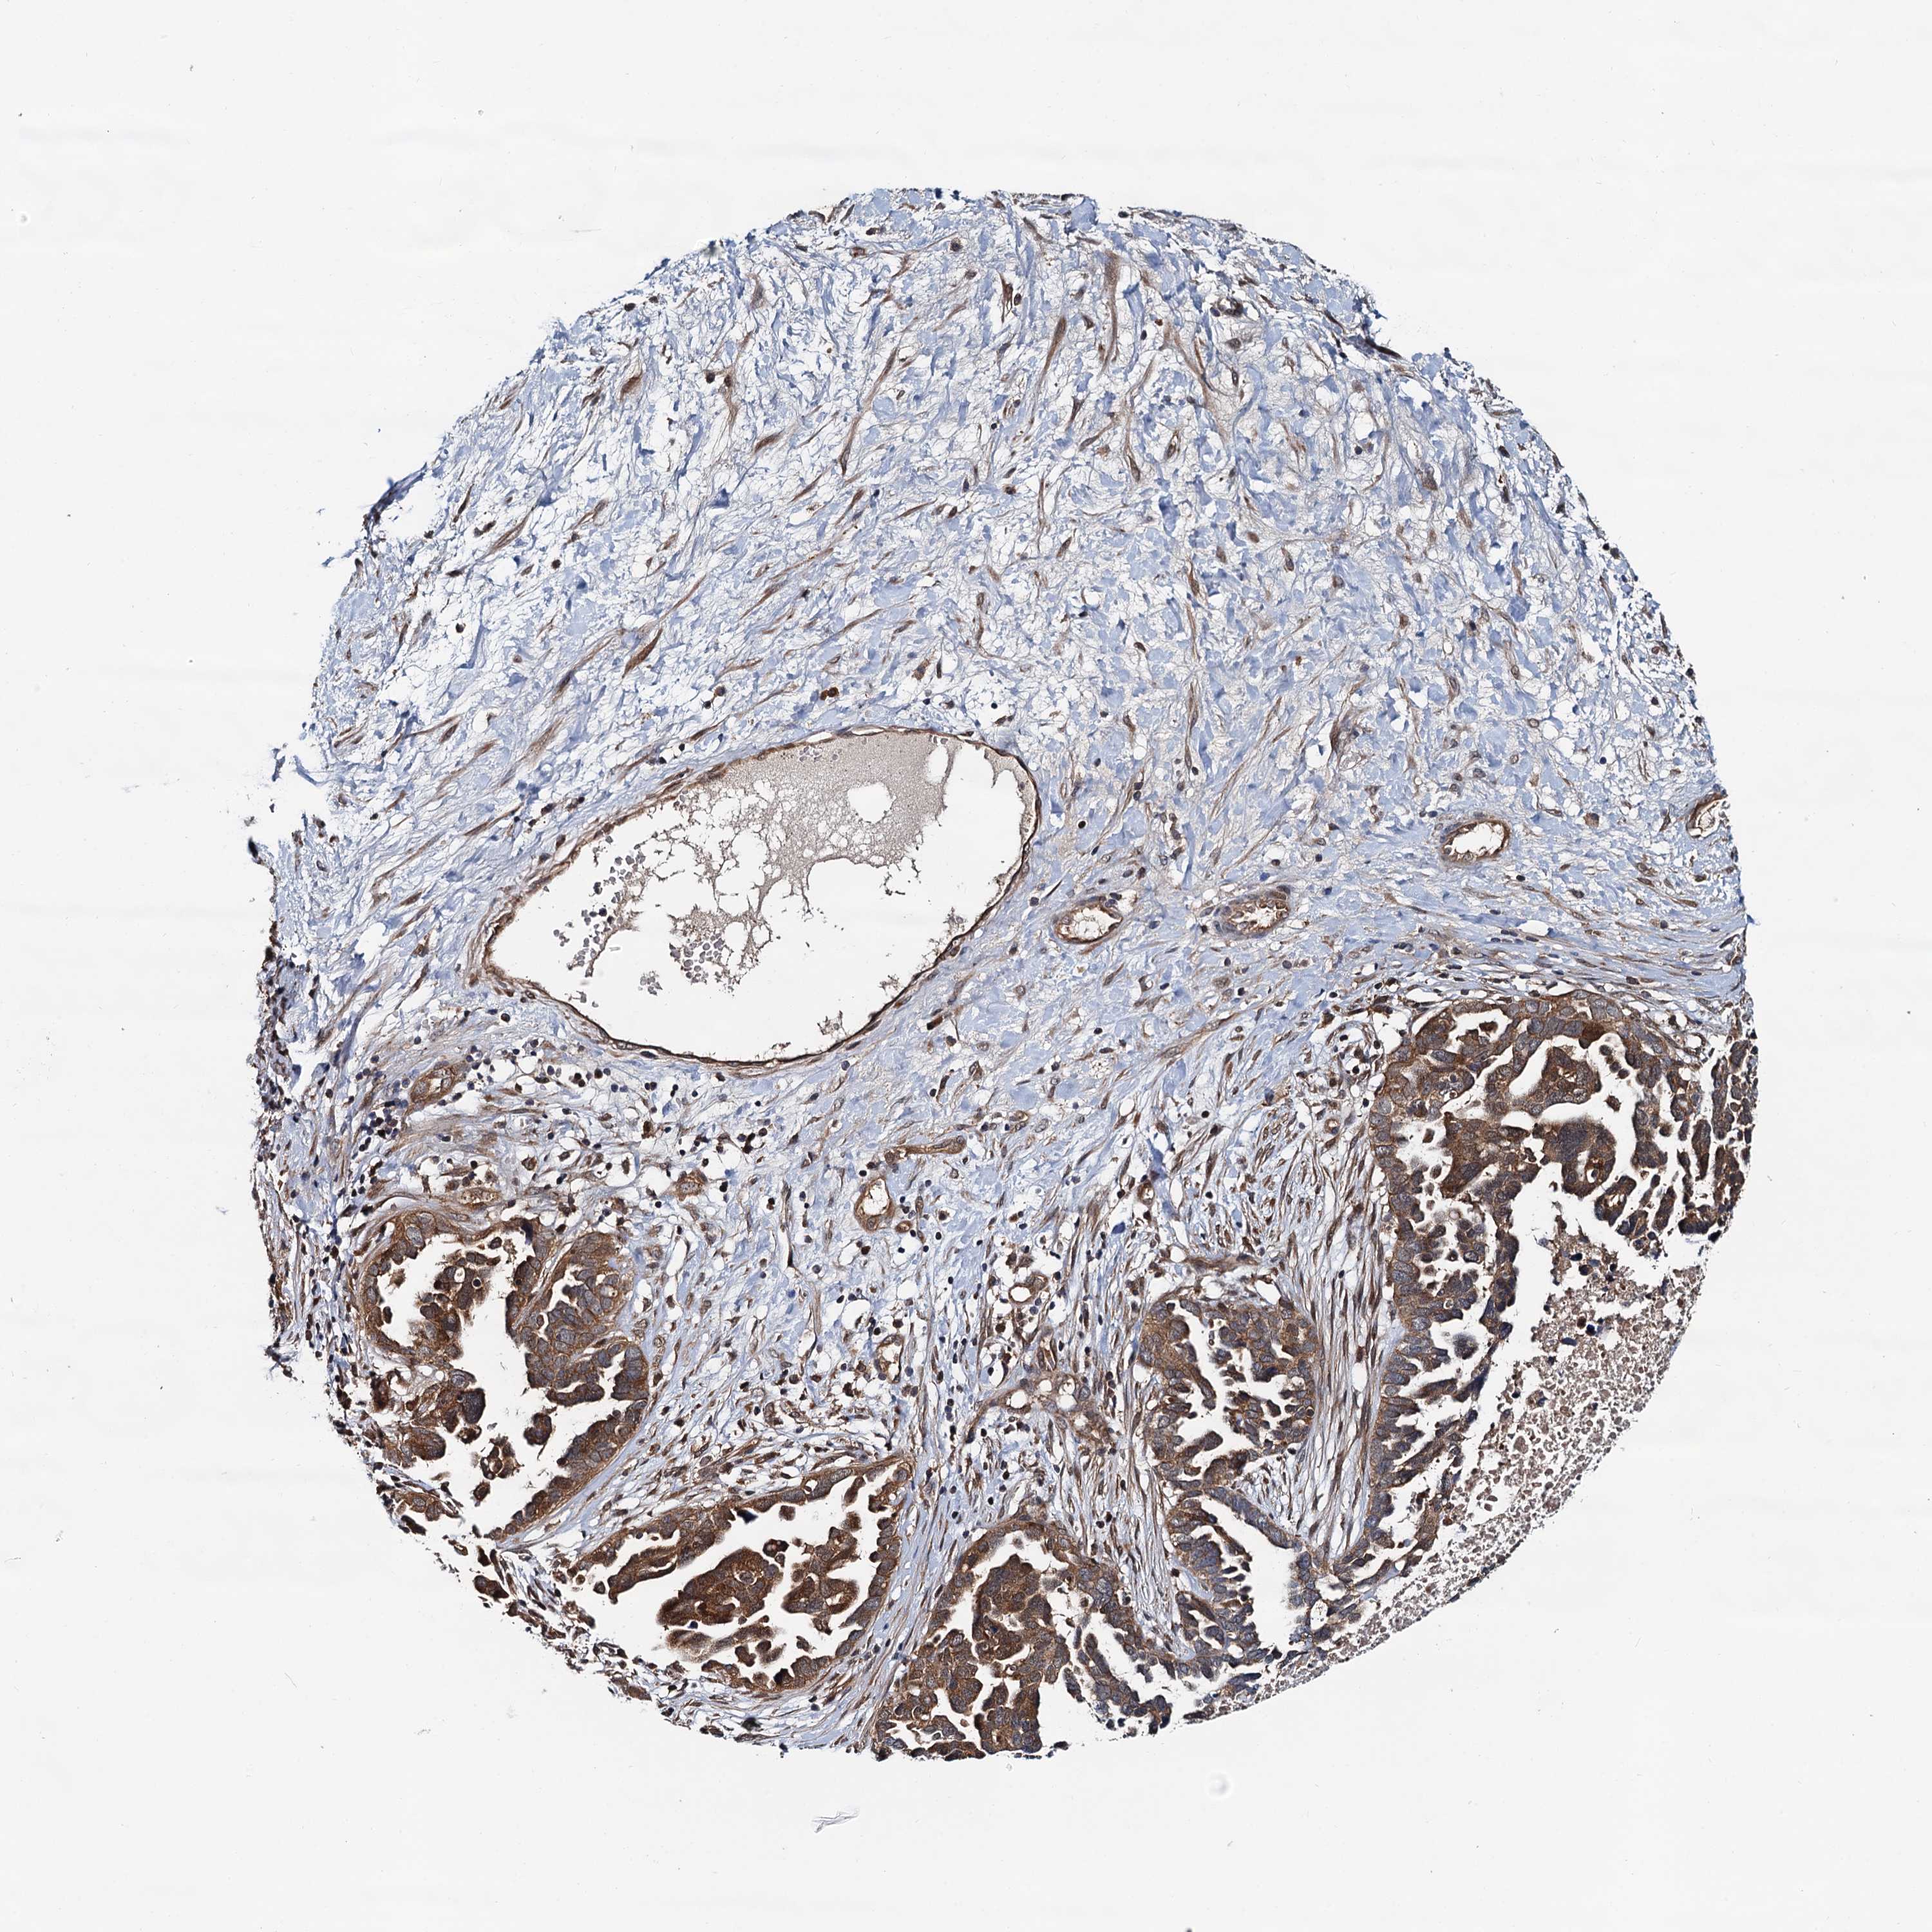

OVARIAN CANCER - Protein expressioni

A mouse-over function shows sample information and annotation data. Click on an image to view it in a full screen mode. Samples can be filtered based on level of antibody staining by selecting one or several of the following categories: high, medium, low and not detected. The assay and annotation is described here.

Note that samples used for immunohistochemistry by the Human Protein Atlas do not correspond to samples in the TCGA dataset.

Antibody stainingi

Antibody staining in the annotated cell types in the current human tissue is reported as not detected, low, medium, or high, based on conventional immunohistochemistry profiling in selected tissues. This score is based on the combination of the staining intensity and fraction of stained cells.

Each image is clickable and will lead to virtual microscopy that enables deeper exploration of all samples and also displays staining intensity scores, fraction scores and subcellular localization as well as patient and tissue information for each sample.

Antibody HPA039371

Antibody HPA040174

Cystadenocarcinoma, serous, NOS

Carcinoma, endometroid

Cystadenocarcinoma, mucinous, NOS

Carcinoma, NOS